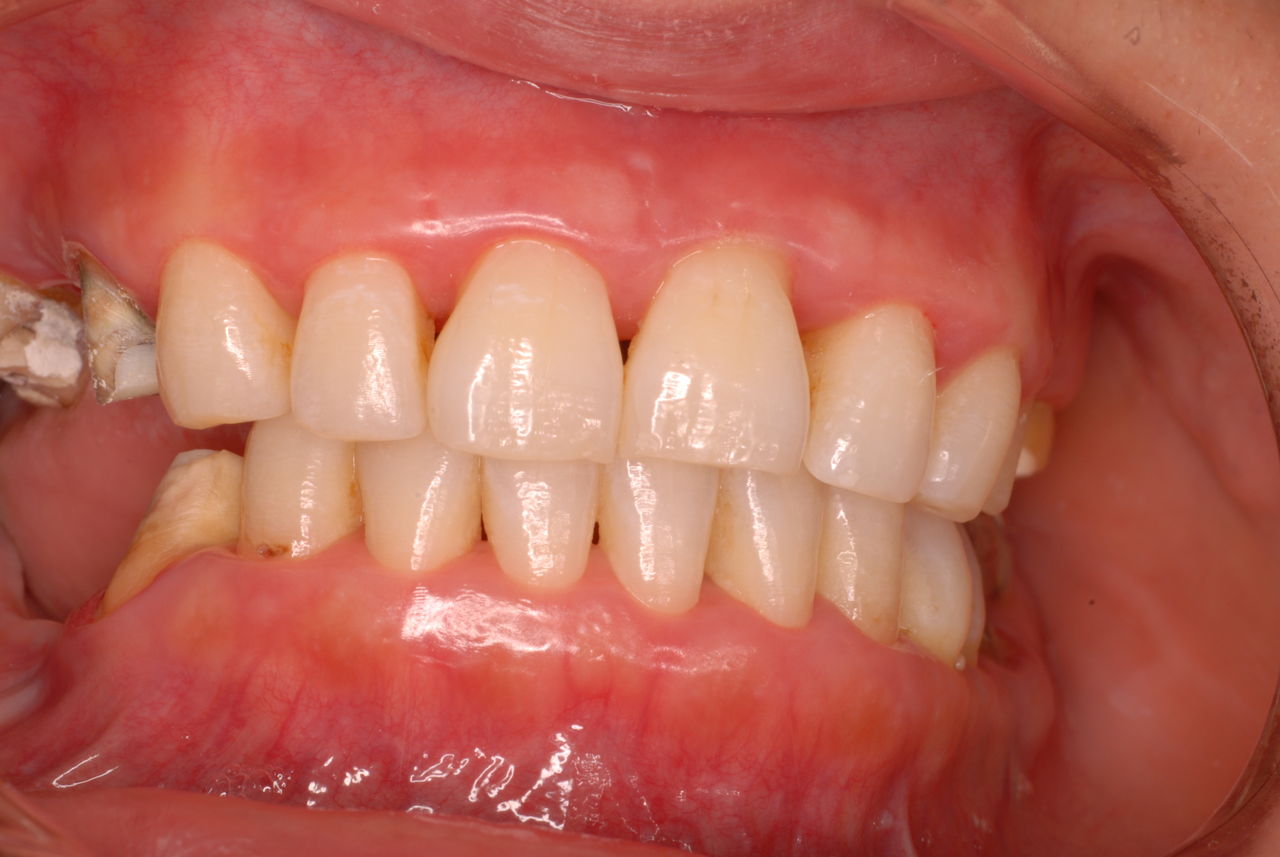

なかなかブラシの使い方ができていないようで、歯磨きと歯周病でのブラシの使い方は別なのですが、習ったことも検査もされずに金属を被せたりしているようで、これからも歯医者さんで抜かれたり、その後にインプラントのような高価な“クギ”を打ち込まれる方が増えるかと思うと残念です。

被せても、詰めても病気は治らないのですから。又病気の元になり易い不適合な差し歯や金属、インプラントがあればそこからバイキンが侵入して体に悪さもしやすいのではないかと心配しています。